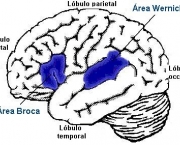

Não há cura para esta doença, não existe meios de simplesmente fazer com que a pessoa recupere a capacidade que perdeu. Entretanto, há tratamentos efetivos que se estimulam as partes do cérebro envolvidas neste processo, para que a pessoa possa voltar a dominar a fala, a escrita e leitura.